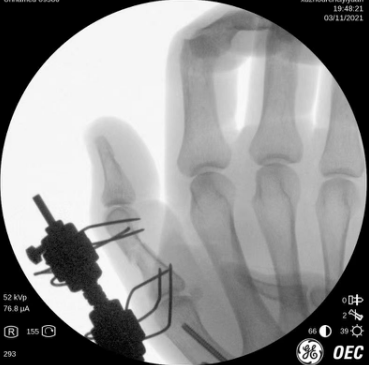

术中透视

术前工作准备完毕,齐伟亚、刘桂谦手术团队为张师傅进行了进行了关节镜辅助下左桡骨远端骨折复位内固定+滑膜清扫,机器人导航下左腕钩状骨骨折复位内固定,左手第1掌骨骨折复位内固定,左拇指近节指骨骨折外固定架外固定,虽然手术时间稍长,但是手术很顺利,术后张师傅恢复良好,张师傅一家称赞齐主任的医技好,而且从患者的角度出发,不让患者多花一分钱。

很快,齐主任组织医疗团队讨论手术方案,齐伟亚、刘桂谦医疗团队参与手术。大家一致认为张师傅左手多处骨折,如果手术可同时使用腕关节镜、天玑骨科机器人及外固定架进行辅助。这样设计优势明显,不但手术次数少,减轻患者痛苦,而且花费少,恢复快,患者和家属满意。